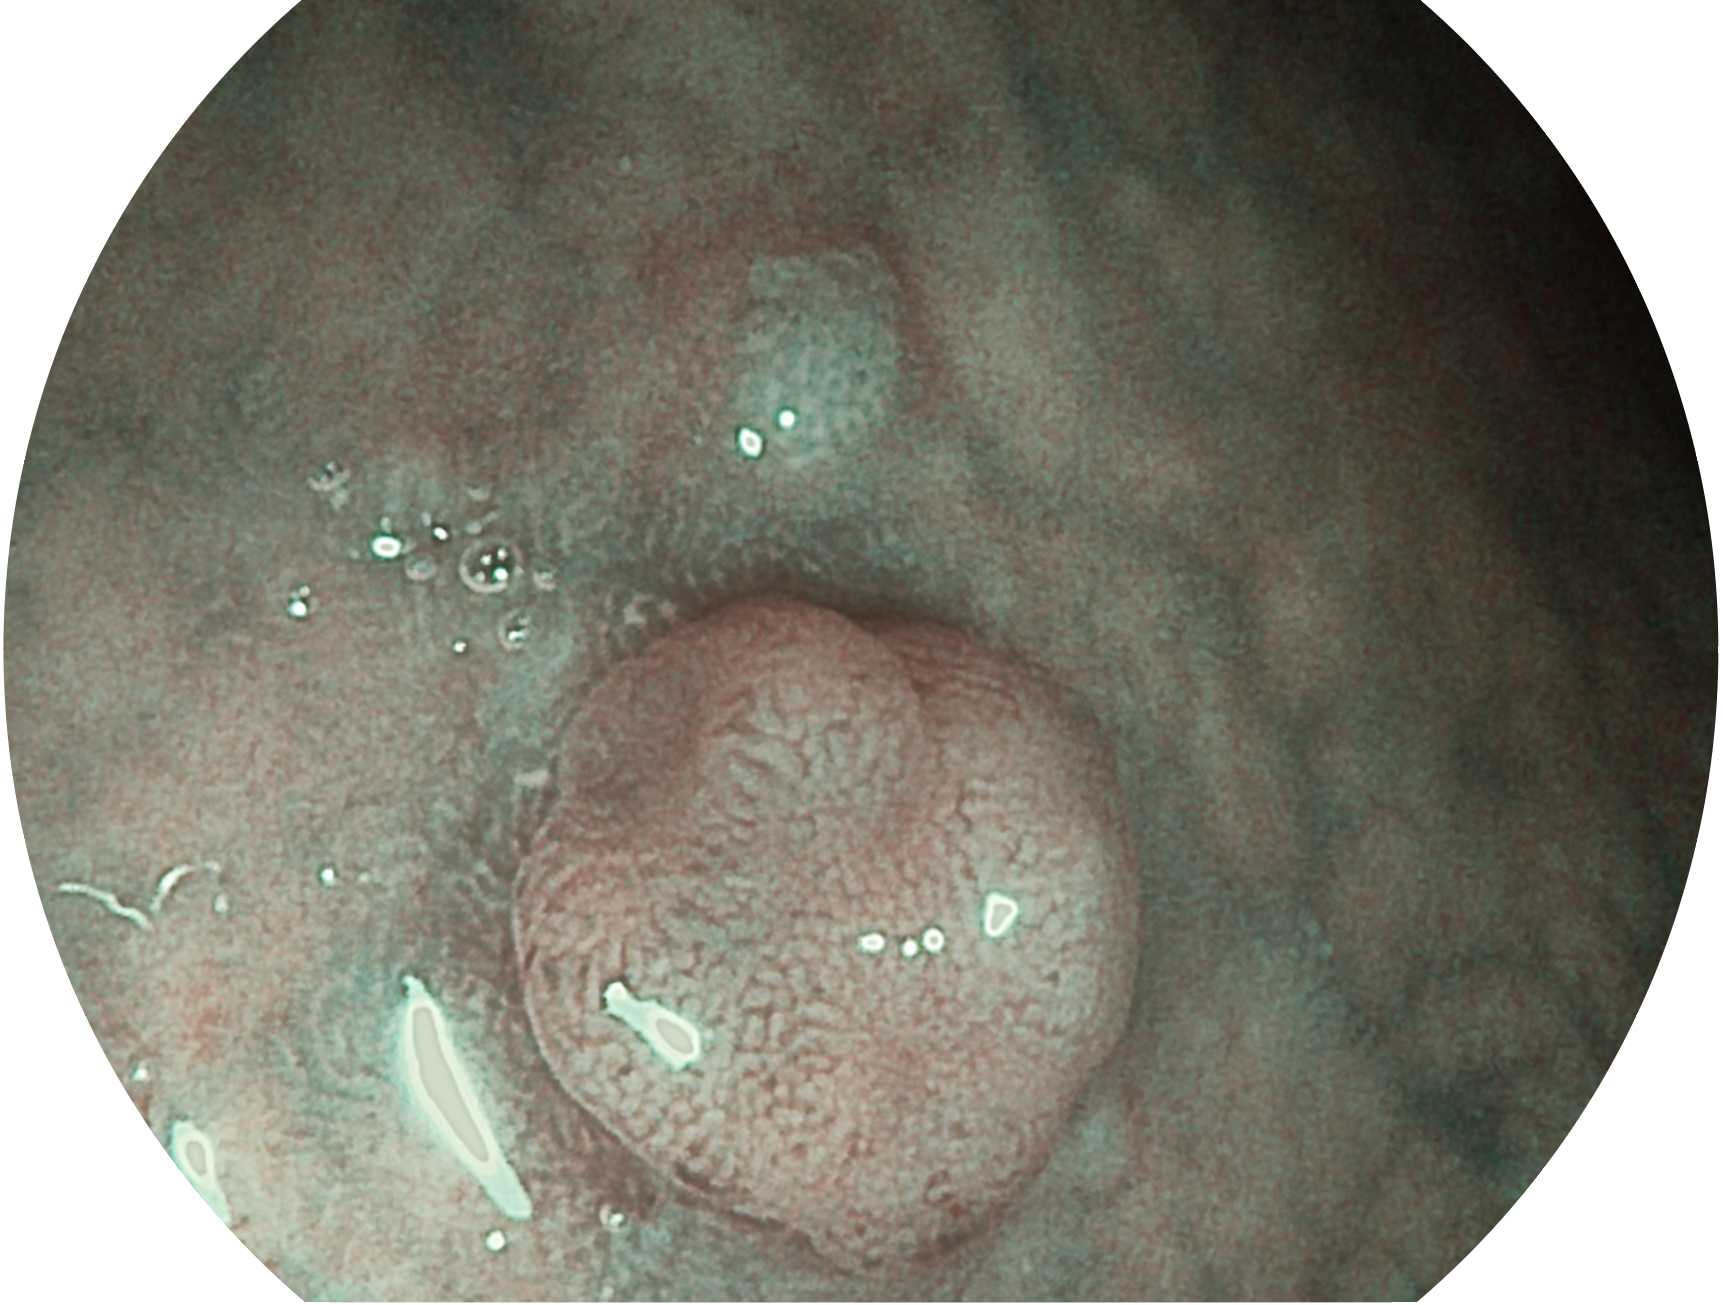

球速体育入口新开发的内镜染色技术,主要是基于多波长LED 光源的开发,VLS-55Q 四波长LED 光源是由四个不同颜色的LED光按照相应照明模式所规定的特定发光比例进行合束后形成,合束后形成的照明光的光谱由红光、绿光、蓝光及蓝紫光这四个不同的波段范围构成。具有更高光谱自由度,通过光谱比例的控制,实现了聚谱成像技术,英文全称为“Spectral Focused Imaging, SFI”,缩写为“SFI”和光电复合染色成像技术,英文全称为“Versatile Intelligent Staining Technology, VIST”,缩写为“VIST”。